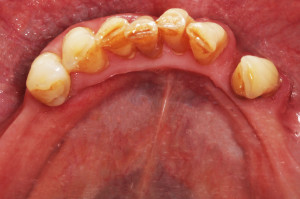

Na drugiej wizycie przeprowadzono dokładną kontrolę pozabiegową. Oznaczono ponownie wszystkie wskaźniki notując znaczną poprawę – API 17%, PBI 33%, sprawdzono głębokość kieszonek i ruchomości zębów.

Płytkę bakteryjną stwierdzono tylko w jednęj przestrzeni, krwawienie w dwóch, niektóre kieszonki spłyciły się. Niestety pani odłożyły się nowe złogi kamienia przy zębach siecznych. Przeprowadzono dokładny instruktaż szczotkowania i nitkowania, dobrano dla pacjentki odpowiednie środki do codziennej higieny jamy ustnej: szczoteczki międzyzębowe , pasty, płukanki, nici oraz skierowano dalej do periodontologa w celu przeprowadzenia dokładnego badania głębokości kieszonek i ewentualnego zabiegu root planingu .